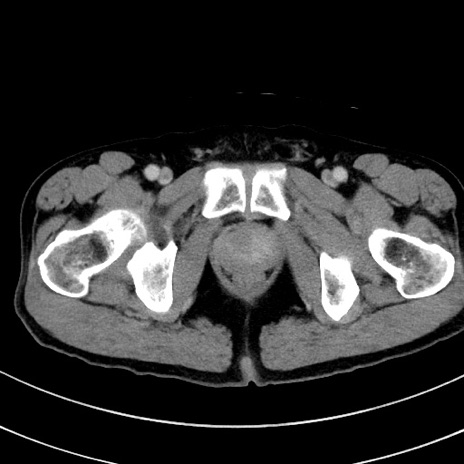

症例8(横断像)

【症例】 60歳代男性

【主訴】 黒色吐物

【現病歴】 4日前から嘔気自覚、2日前の朝食後にも嘔気あり、自分で手で嘔吐反射起こし嘔吐したところ血が混ざっていたため受診。

【既往歴】 5年前汎発性腹膜炎を伴う急性虫垂炎で手術、高血圧、前立腺肥大症、高脂血症

【身体所見】 腹部正中に手術癩痕あり 腹部平坦・軟圧痛なし膨満感あり

【データ】WBC 8400、CRP 4.54